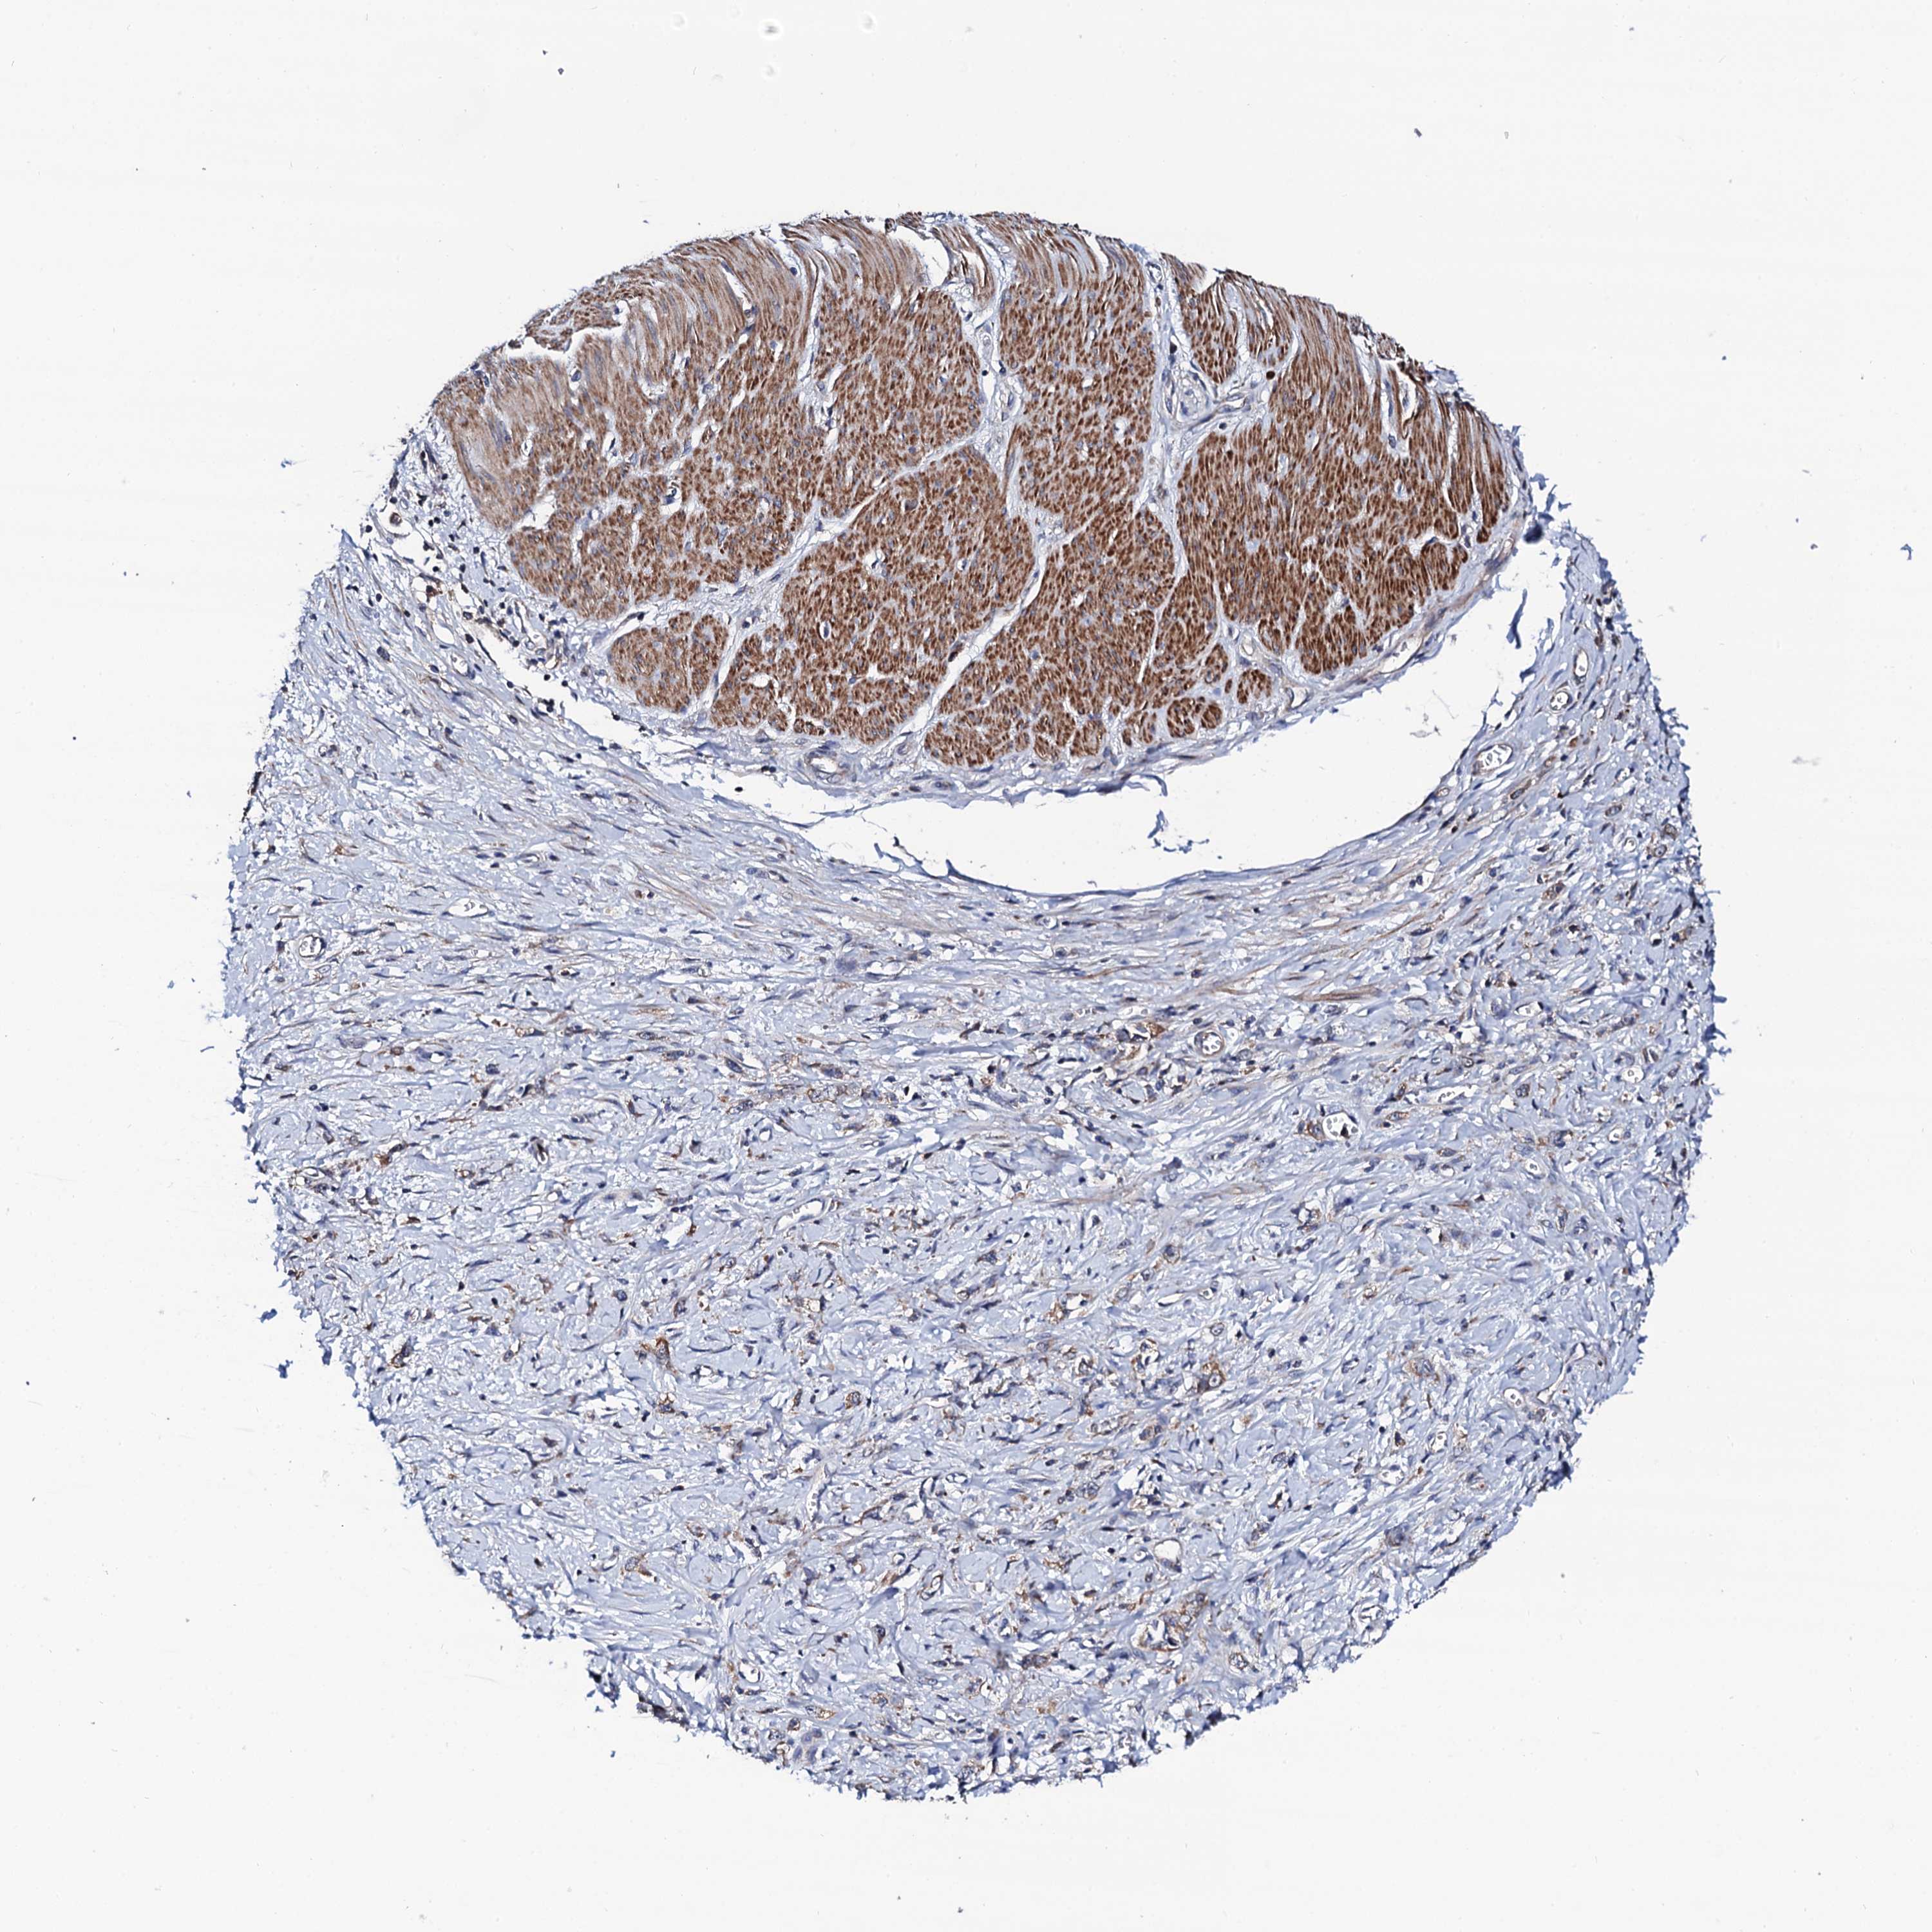

STOMACH CANCER - Protein expressioni

A mouse-over function shows sample information and annotation data. Click on an image to view it in a full screen mode. Samples can be filtered based on level of antibody staining by selecting one or several of the following categories: high, medium, low and not detected. The assay and annotation is described here.

Note that samples used for immunohistochemistry by the Human Protein Atlas do not correspond to samples in the TCGA dataset.

Antibody stainingi

Antibody staining in the annotated cell types in the current human tissue is reported as not detected, low, medium, or high, based on conventional immunohistochemistry profiling in selected tissues. This score is based on the combination of the staining intensity and fraction of stained cells.

Each image is clickable and will lead to virtual microscopy that enables deeper exploration of all samples and also displays staining intensity scores, fraction scores and subcellular localization as well as patient and tissue information for each sample.

Antibody HPA040924

Antibody HPA042539

Staining

High

Medium

Low

Not detected

Intensity

Strong

Moderate

Weak

Negative

Quantity

>75%

75%-25%

<25%

None

Location

Nuclear

Cytoplasmic/membranous

Cytoplasmic/membranous,nuclear

Adenocarcinoma, NOS

Adenocarcinoma, High grade